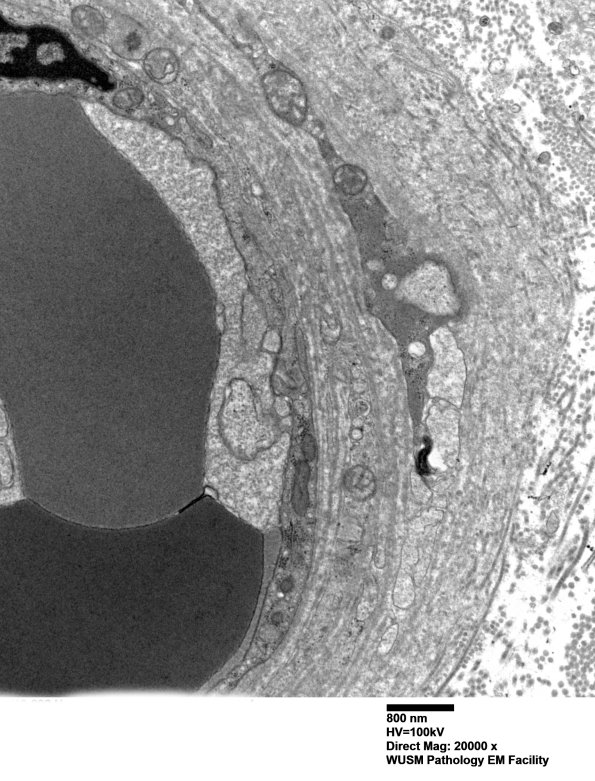

Multiple magnifications of a mildly enlarged vessel which has been expanded by collagen deposition. (electron micrographs)